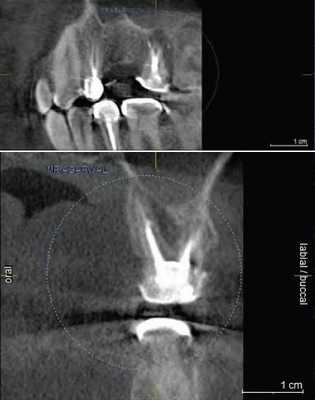

Сверхкомплектный зуб определен как парамоляр. Коронка парамоляра имела два бугорка и весьма сильно напоминала строение постоянного премоляра. Зуб повернут по оси, с расположением щечной поверхности дистально и мезиальной поверхности щечно. На мезиальной стороне парамоляра обнаружено кариозное поражение (Фото 2). Осмотр мягких тканей выявил воспаление пародонта между первым и вторым молярами и парамоляром. Сделаны рентгеновские снимки: панорамный, прицельный и окклюзионный. Чтение панорамного снимка было затруднено из-за небного расположения зуба. На прицельном и окклюзионных снимках обнаружено, что сверхкомплектный зуб поражен кариесом и имеет один корень (Фото 3 и 4).

Удаленный зуб очищен, дезинфицирован и проанализирован. Морфология зуба нормальная. Длина корня соответствует размерам коронки. Апекс корня полностью развит. Рентгенологическое исследование выявило I тип конфигурации канала (Vertucci). Фактические размеры зуба: мезиодистальная и щечно-небная ширина коронки 6 и 10 мм соответственно, длина коронки 6,5 мм, длина корня 12 мм. Морфометричечкие измерения показали высокую схожесть сверхкомплектного зуба с премоляром (Фото 2).

Фото 2: Фотографии удаленного зуба: (a) окклюзионный вид, (b) мезиальный, (с) дистальный, (d) щечный, (e) небный.